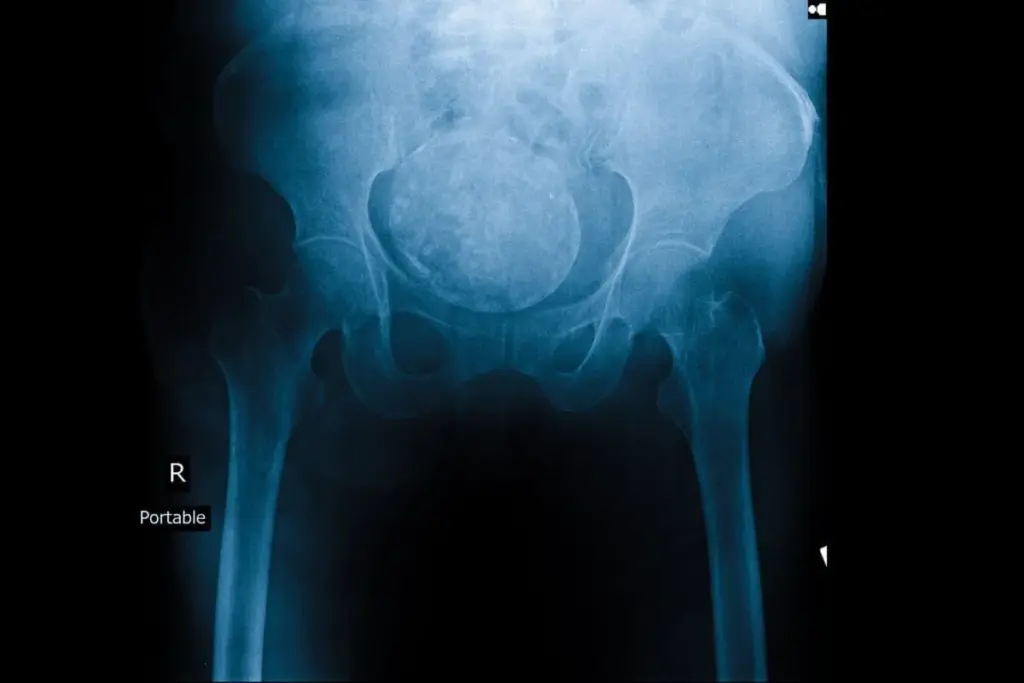

Ovarian cancer is a big challenge in healthcare, hitting women all over the world. It comes in different types and stages. The American Cancer Society says it’s a top cause of death in gynecologic cancers.